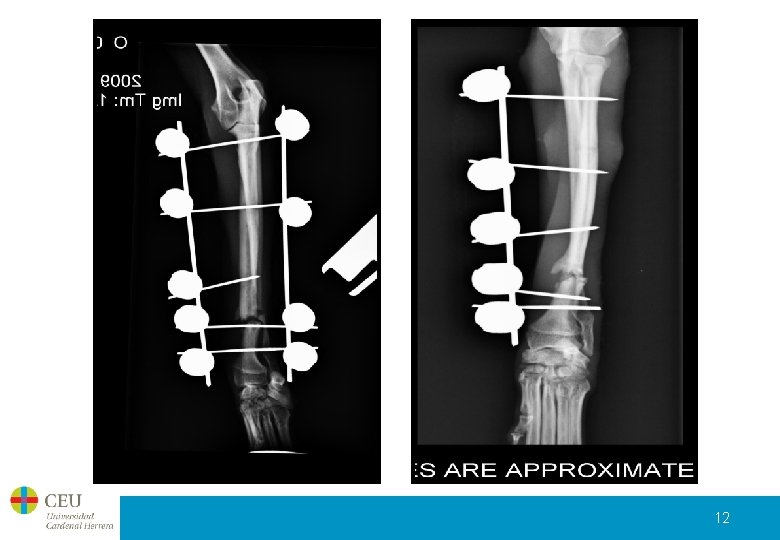

Control post-quirúrgico Un mes después de la intervención: • Evaluamos el fijador externo y observamos que la aguja superior cercana a la articulación supura y presenta movimiento. Además, la 4ª aguja está demasiado cerca del foco de fractura; cosa de la que, anteriormente ya nos habíamos dado cuenta pero fue este día cuando se decidió intervenir quirúrgicamente de nuevo a la paciente. • Redireccionamos las 2 agujas y quitamos el fijador lateral. 11

12